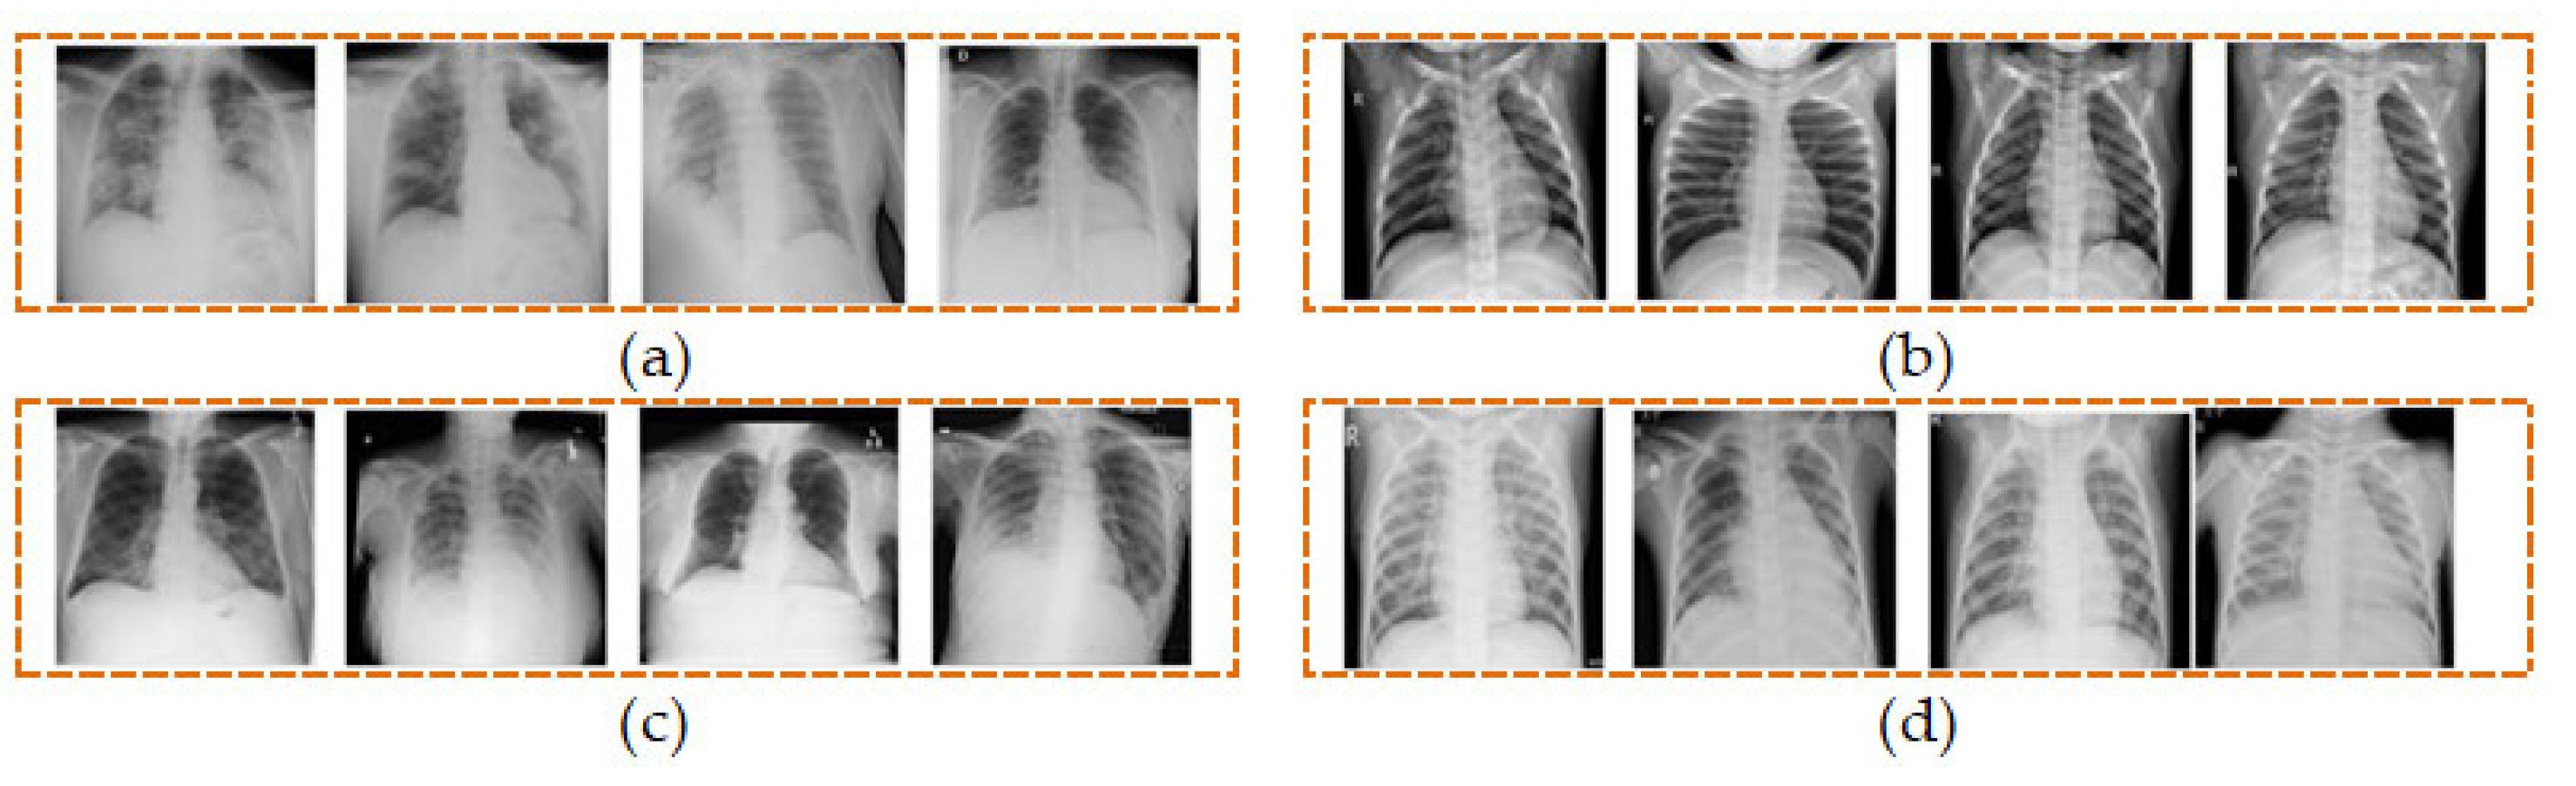

We have utilized a total of 5360 CXR images from the four different classes comprising of COVID-19, normal, lung opacity, and viral pneumonia, each of which contains an equal number of 1340 images as shown in Table 1. Four sample CXR images from each class are shown in Figure 2.

Figure 2.

Samples of CXR images from four classes of (a) COVID-19, (b) normal, (c) lung opacity, and (d) viral pneumonia.